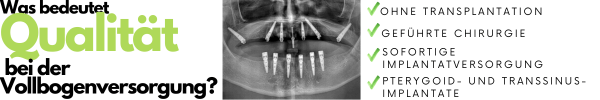

Dr. Rafid Hussain, der leitende Zahnimplantatchirurg am Sofia Implant Centre, führte kürzlich die erste Pterygoid-Implantation in Bulgarien durch. Möglich wurde dies durch den Einsatz von Bohrschablonen und innovativen digitalen Protokollen, die eine hochpräzise Platzierung von Zahnimplantaten im Pterygoidknochen ermöglichen und eine sichere Grundlage für eine vollständige Zahnbogenrestauration auf Basis von 6 Implantaten (ALL-ON-6) bieten.